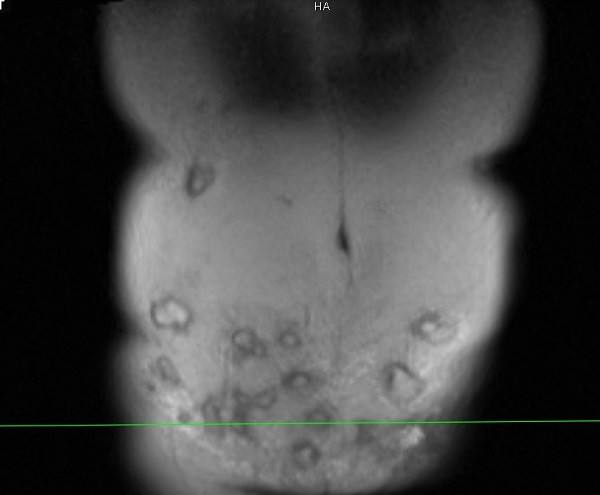

Ngày 4/10, Thạc sĩ, bác sĩ Nguyễn Đình Minh, Trưởng khoa Phẫu thuật tạo hình, thẩm mỹ và hàm mặt (Bệnh viện E, Hà Nội) cho biết, vừa tiếp nhận nữ bệnh nhân tên H.T.T (43 tuổi) nhập viện trong tình trạng vùng thành bụng dưới xuất hiện hàng loạt ổ áp xe.

Spa này tiêm rất nhiều mũi vào thành bụng dưới của bệnh nhân, đồng thời tiêm cả trên vùng hạ sườn hai bên. Sau tiêm khoảng 1 tháng, chị T. đau vùng bụng dưới và tới Bệnh viện E để thăm khám, tạo hình lại thành bụng.

Bác sĩ Minh cho biết, vùng thành bụng bệnh nhân bị viêm phản ứng nặng, vùng da ngoài thành bụng đỏ, nổi gồ ghề, sờ bên dưới có hàng chục khối tổ chức vón cục, áp xe....

“Bệnh nhân này có thể tạo hình lại thành bụng, đồng thời giải quyết được 20 khối áp xe lớn nhỏ. Tuy nhiên, do vùng tiêm rộng nên việc lấy hết ổ áp xe này không dễ dàng. Với những khối áp xe tiêm ở vị trí cao như hạ sườn thì quá trình xử lý sẽ để lại sẹo, gây mất thẩm mỹ”, bác sĩ Minh chia sẻ.